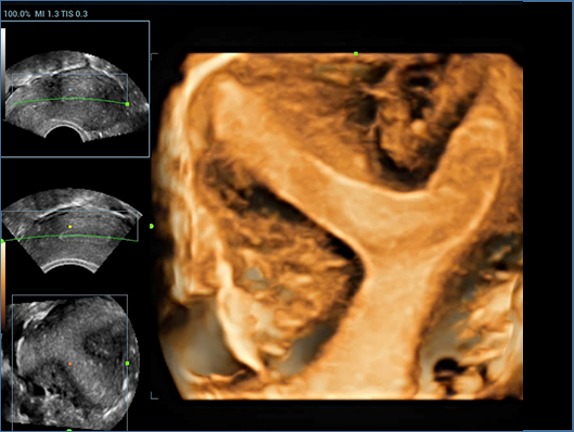

Resona 7, ĂŒstĂŒn dĂŒzeyde g?rĂŒntĂŒ kalitesine ek olarak, vaskĂŒler hemodinamik de?erlendirmesi i?in devrim niteli?indeki V Ak??? ile fetĂŒs CNS tan?lamas? i?in 3 boyutlu veri kĂŒmesinden dĂŒzlem g?rĂŒntĂŒsĂŒ alma konusunda en iyi birime sahip oldu?undan, klinik ara?t?rma yeterliklerini de art?rmaktad?r. En sezgisel, harekete dayal? ?oklu dokunmatik i?letim ile tĂŒm temel klinik ?zellikleri bir araya getiren Resona 7, ultrason yenili?i konusunda ger?ek anlamda yeni dalgalara ?ncĂŒlĂŒk ediyor.